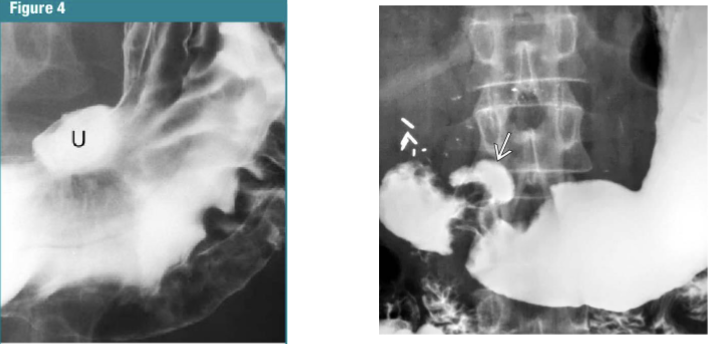

What is this and what type of scan

Peptic ulcer disease, barium swallow